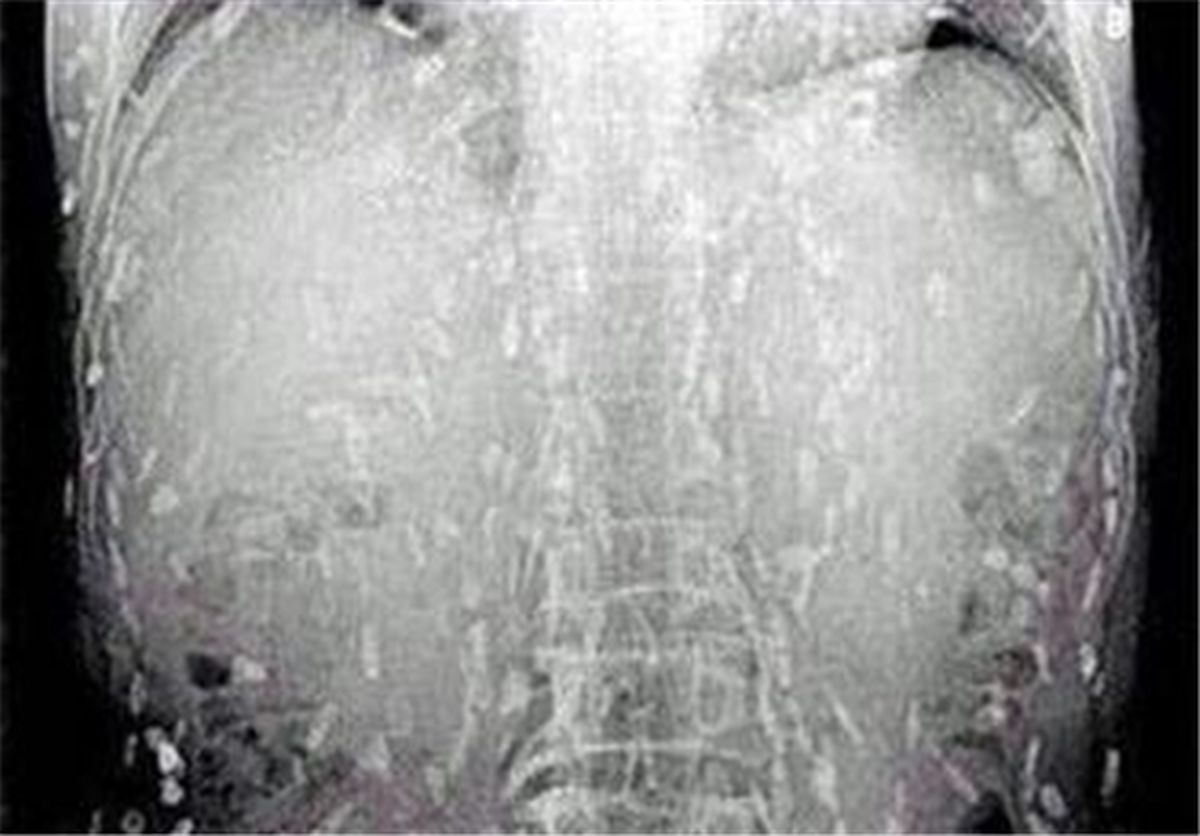

مردی آمریکایی به علت معدهدرد شدید و خارش در سراسر پوست نزد دکتر رفت و پس از انجام اسکن از کل بدن، دکتر متوجه شد دهها کرم نواری در بدن او وجود دارد.